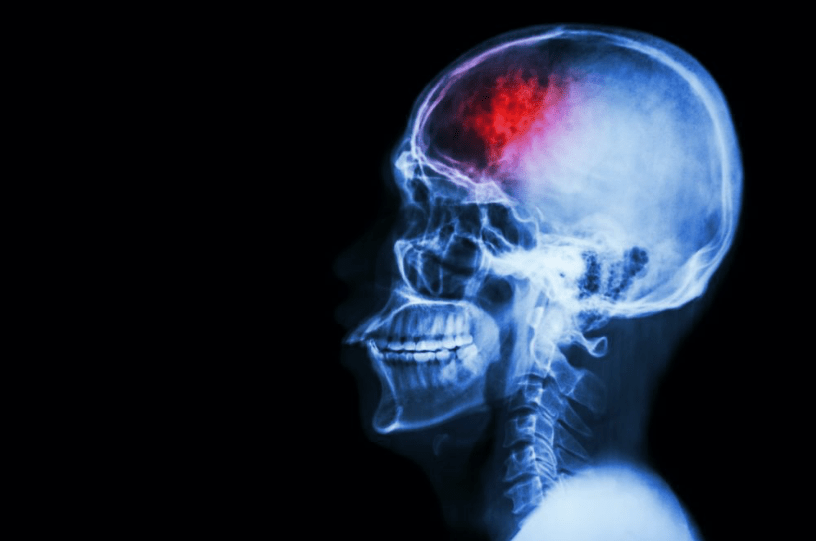

Brain cancer could be triggered by the healing process from a brain injury, new research has said, in findings which could yield new breakthroughs in patient therapies.

The tumours of 26 patients with glioblastoma were analysed in the Canadian research project, and found that mutations can affect the process of new cells being created, which can therefore stimulate tumour growth. “Our data suggests that the right mutational change in particular cells in the brain could be modified by injury to give rise to a tumour,' says report author and neurosurgeon Peter Dirks, from The Hospital for Sick Children in Toronto. “Glioblastoma can be thought of as a wound that never stops healing.Growing demand is expected from people with brain injuries and neurological conditions in accessing support with mental health, Long COVID and employment rights, a specialist charity has revealed.